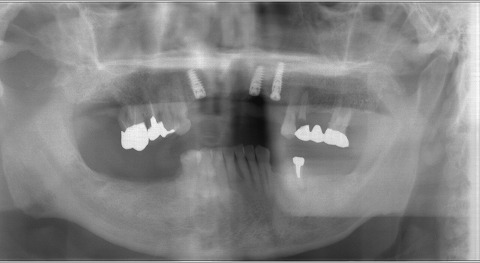

ノーベルアクティブの13mmが2本と15mmが1本です。

ノーベルアクティブは、先月やっと日本で認可が下りたばかりの

インプラントです。

ただ、世界的には昨年には認可が下りていましたので、

当院では、今年1年で70本ほど埋入しました。